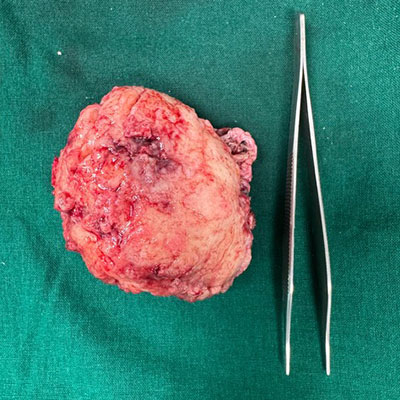

Dr. Ujwal Yeole is an experienced neurosurgeon specializes in treating a wide spectrum of neurological conditions including neuro-oncology, peripheral nerve disorders, vascular disorders, spinal pathologies, pediatric neurosurgery, neuro-trauma and skull base neuroendoscopic procedures.